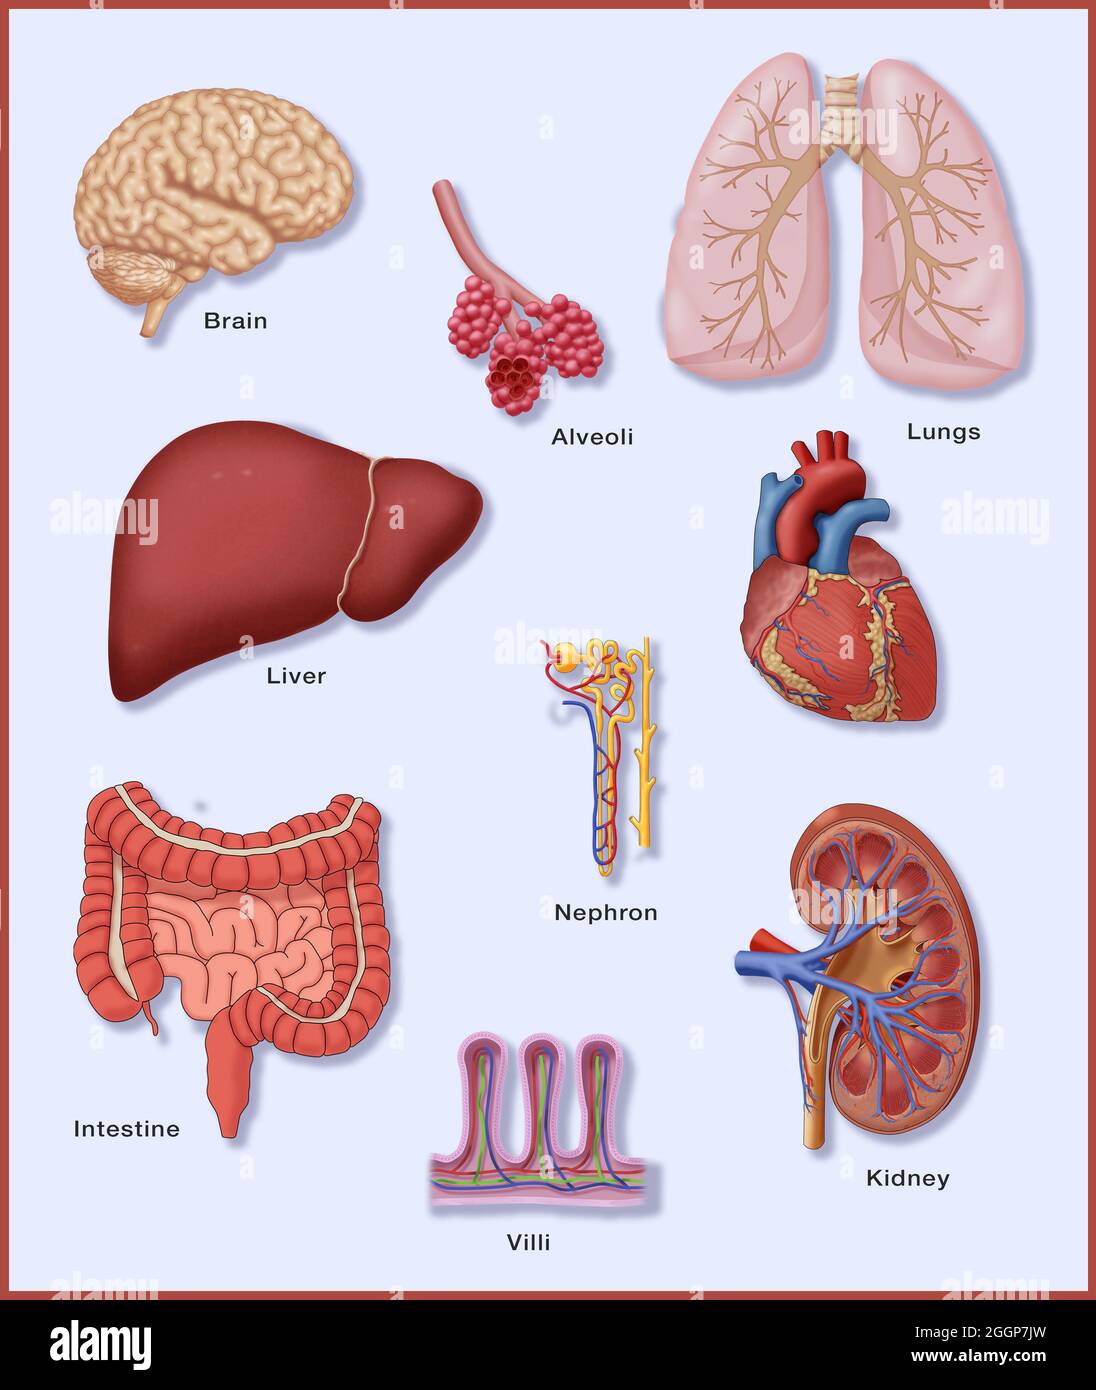

A selection of organs that have delicate vascular systems. Stock Photohttps://www.alamy.com/image-license-details/?v=1https://www.alamy.com/a-selection-of-organs-that-have-delicate-vascular-systems-image440582659.html

A selection of organs that have delicate vascular systems. Stock Photohttps://www.alamy.com/image-license-details/?v=1https://www.alamy.com/a-selection-of-organs-that-have-delicate-vascular-systems-image440582659.htmlRM2GGP7JY–A selection of organs that have delicate vascular systems.

A selection of organs that have delicate vascular systems. Stock Photohttps://www.alamy.com/image-license-details/?v=1https://www.alamy.com/a-selection-of-organs-that-have-delicate-vascular-systems-image440582646.html

A selection of organs that have delicate vascular systems. Stock Photohttps://www.alamy.com/image-license-details/?v=1https://www.alamy.com/a-selection-of-organs-that-have-delicate-vascular-systems-image440582646.htmlRM2GGP7JE–A selection of organs that have delicate vascular systems.

A selection of organs that have delicate vascular systems. Stock Photohttps://www.alamy.com/image-license-details/?v=1https://www.alamy.com/a-selection-of-organs-that-have-delicate-vascular-systems-image440582624.html

A selection of organs that have delicate vascular systems. Stock Photohttps://www.alamy.com/image-license-details/?v=1https://www.alamy.com/a-selection-of-organs-that-have-delicate-vascular-systems-image440582624.htmlRM2GGP7HM–A selection of organs that have delicate vascular systems.

A selection of organs that have delicate vascular systems. Stock Photohttps://www.alamy.com/image-license-details/?v=1https://www.alamy.com/a-selection-of-organs-that-have-delicate-vascular-systems-image440582657.html

A selection of organs that have delicate vascular systems. Stock Photohttps://www.alamy.com/image-license-details/?v=1https://www.alamy.com/a-selection-of-organs-that-have-delicate-vascular-systems-image440582657.htmlRM2GGP7JW–A selection of organs that have delicate vascular systems.